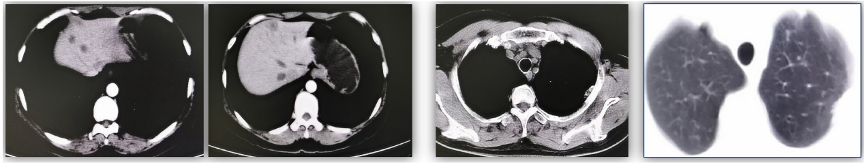

⑤一线治疗:给予GP方案(吉西他滨+顺铂)化疗6周期,左肺胸膜下病变无变化。肝转移灶部分较前增大(图2)。

图2. 肝最大病灶直径1.2 cm(2017年12月,左图),肝最大病灶直径3.8 cm(2018年6月,右图)

2018年7月至2019年4月:氟维司群(500 mg 肌注 d1、15,以后每28天一次)+戈舍瑞林3.6 mg/月治疗(10个月),定期每3月复查。复查CT肝转移灶缩小,左肺胸膜下病灶无变化(图3)。

图3. 肝最大病灶直径3.8 cm(2018年6月,左图),肝最大病灶直径3.0 cm(2019年4月,右图)

2019年5月至2019年12月,Palbociclib/ target=_blank class=infotextkey>哌柏西利在中国上市后,患者在原来的方案上联合Palbociclib/ target=_blank class=infotextkey>哌柏西利:哌柏西利125 mg/日+氟维司群+戈舍瑞林治疗(8个月),复查肝转移灶再次明显缩小,疗效为部分缓解(PR)(图4)。之后患者因经济原因停用哌柏西利。

图4. 肝最大病灶直径3.0 cm(2019年4月,左图),肝最大病灶直径1.8 cm(2019年12月,右图)